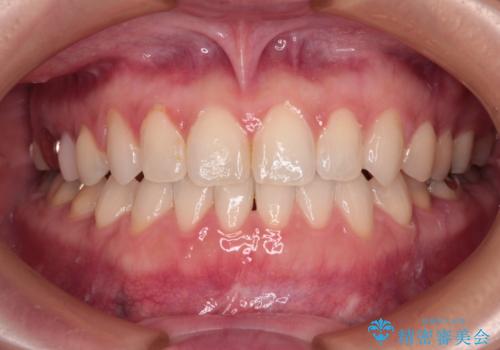

【モニター】処置歯の多い歯列 インビザラインでデコボコを整える